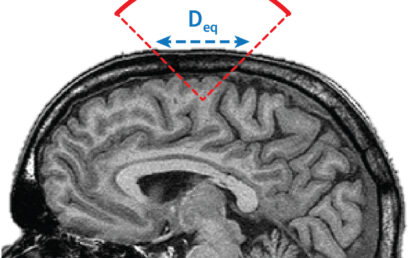

Imaging the brain through the skull: a comprehensive review

How can we see the human brain through the skull?

A new perspective in Nature Biomedical Engineering reviews the complexity of imaging the brain with ultrasound and optical waves.